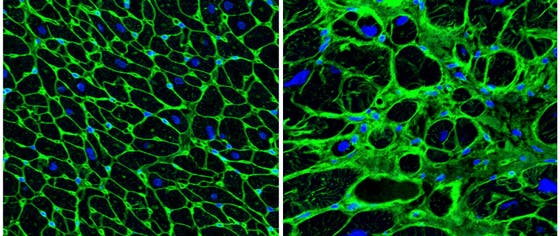

Hypertrophic cardiomyopathy is a heart disease that leads to a stressed, swollen heart muscle. Due to a poor understanding of underlying mechanisms, effective clinical treatments are not available. Patients receive generic heart medication and sometimes need open-heart surgery to remove excess tissue. Researchers at the Hubrecht Institute have now successfully applied a new revolutionary technology (scRNA-seq) to uncover underlying disease mechanisms, including specifically those causing the swelling. The extensive “big data” set is a treasure trove of novel observations that give insight in hypertrophic cardiomyopathy and potential new therapeutic venues. The results from this study, done by researchers in the group of Eva van Rooij, were published in the journal Cell Reports on the 10th of May.